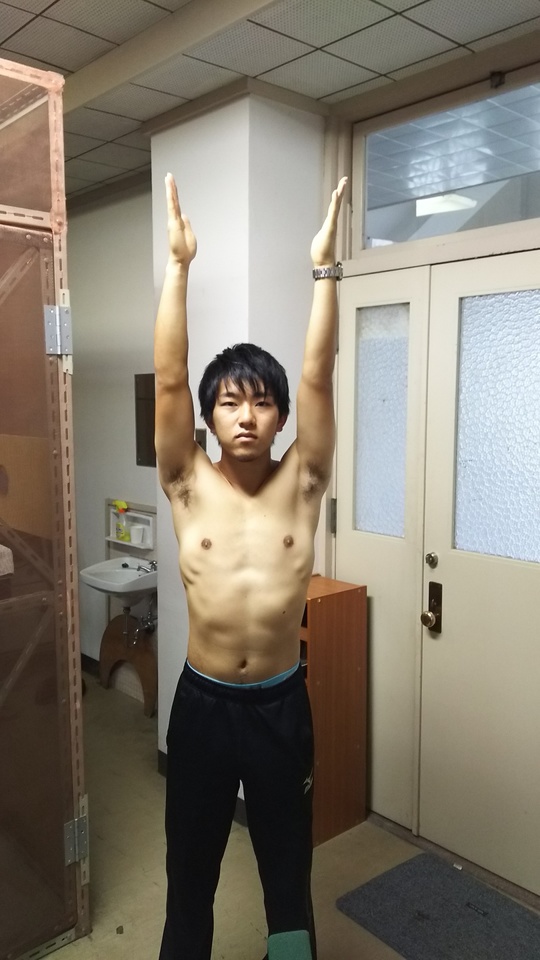

大学3年生アーチェリー選手、2017年3月から弓を肩の高さに引き上げて保持できなくなる。腫れ、熱は無いが腕を横から挙げていくと60度蚊ら90度で痛みが生じ、120度以上は力が入らず180度腕が挙がらない。

近隣医科に行くほど日常生活にも支障なく放置して様子を見ていたが、症状不変。

棘上筋への置鍼(寸3、2番)、その後筋膜リリース3分間。施術時間7分間ほど。

直後効果として、ROM左右さ無く、上肢拳上に支障なし。その2週間後、施術後の状態が維持され、アーチェリー完全復帰。

骨・軟骨・靭帯損傷・神経損傷なく、筋・筋膜・腱の支障による症状の場合は可逆的変化は著明。物理刺激は即時反応を示すが、物理刺激をやめれば反応は消失するのが一般的である。しかし、本症例のように約6か月にも及ぶ傷害であっても、即時効果ならびに持続的効果が確認できた症例である。